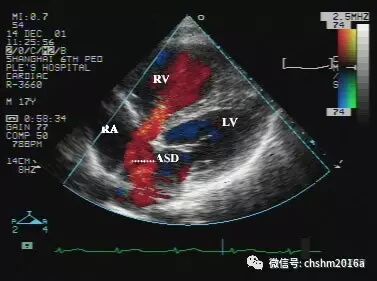

彩色多普勒血流显像房水平左向右分流时,彩色多普勒可显示红色血流穿过房间隔缺损,从左房伸入到右房,直达三尖瓣口。分流束的宽度取决于房间隔缺损的大小。缺损大,分流束宽;缺损小,分流束窄。

图2.3.3   红色的房间隔缺损分流束跨越缺损口进入右房、右室

ASD:房间隔缺损